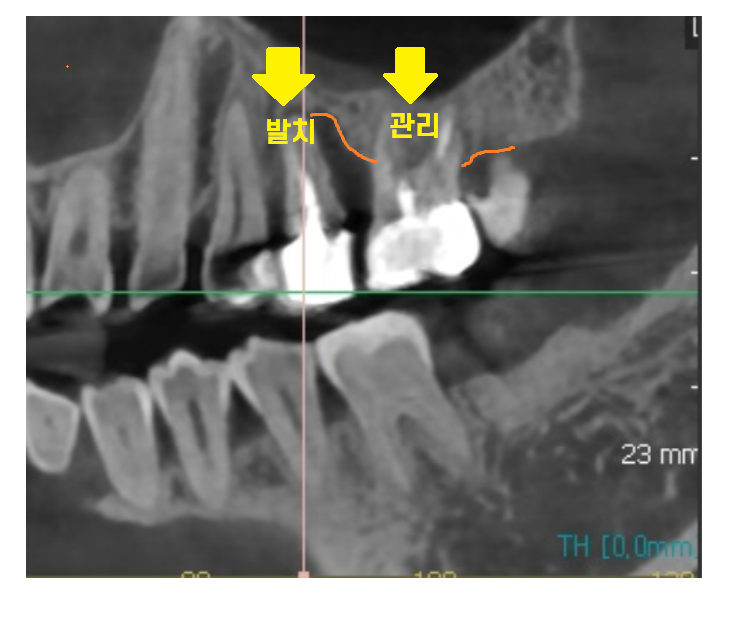

22.12.14

자연 치아를 최대한 살리고

중시하는 저이기에

ct상 문제가 되는

뼈가 많이 녹은 치아 1개만 발치를 말씀드렸는데요.

뒤에 치아도 안좋긴 하지만

잇몸치료도 진행하고

관리하시면서 쓰시라고 말이죠~

환자분은 더 냅둬서 좋을께 없다고

같이 뽑고 싶다 하셨어요!

예전에 무릎도 버티고 버티다

엄청 고생하셨다고 ㅠㅠ

문제되는 치아를 그냥 뽑자 하시더라고요.